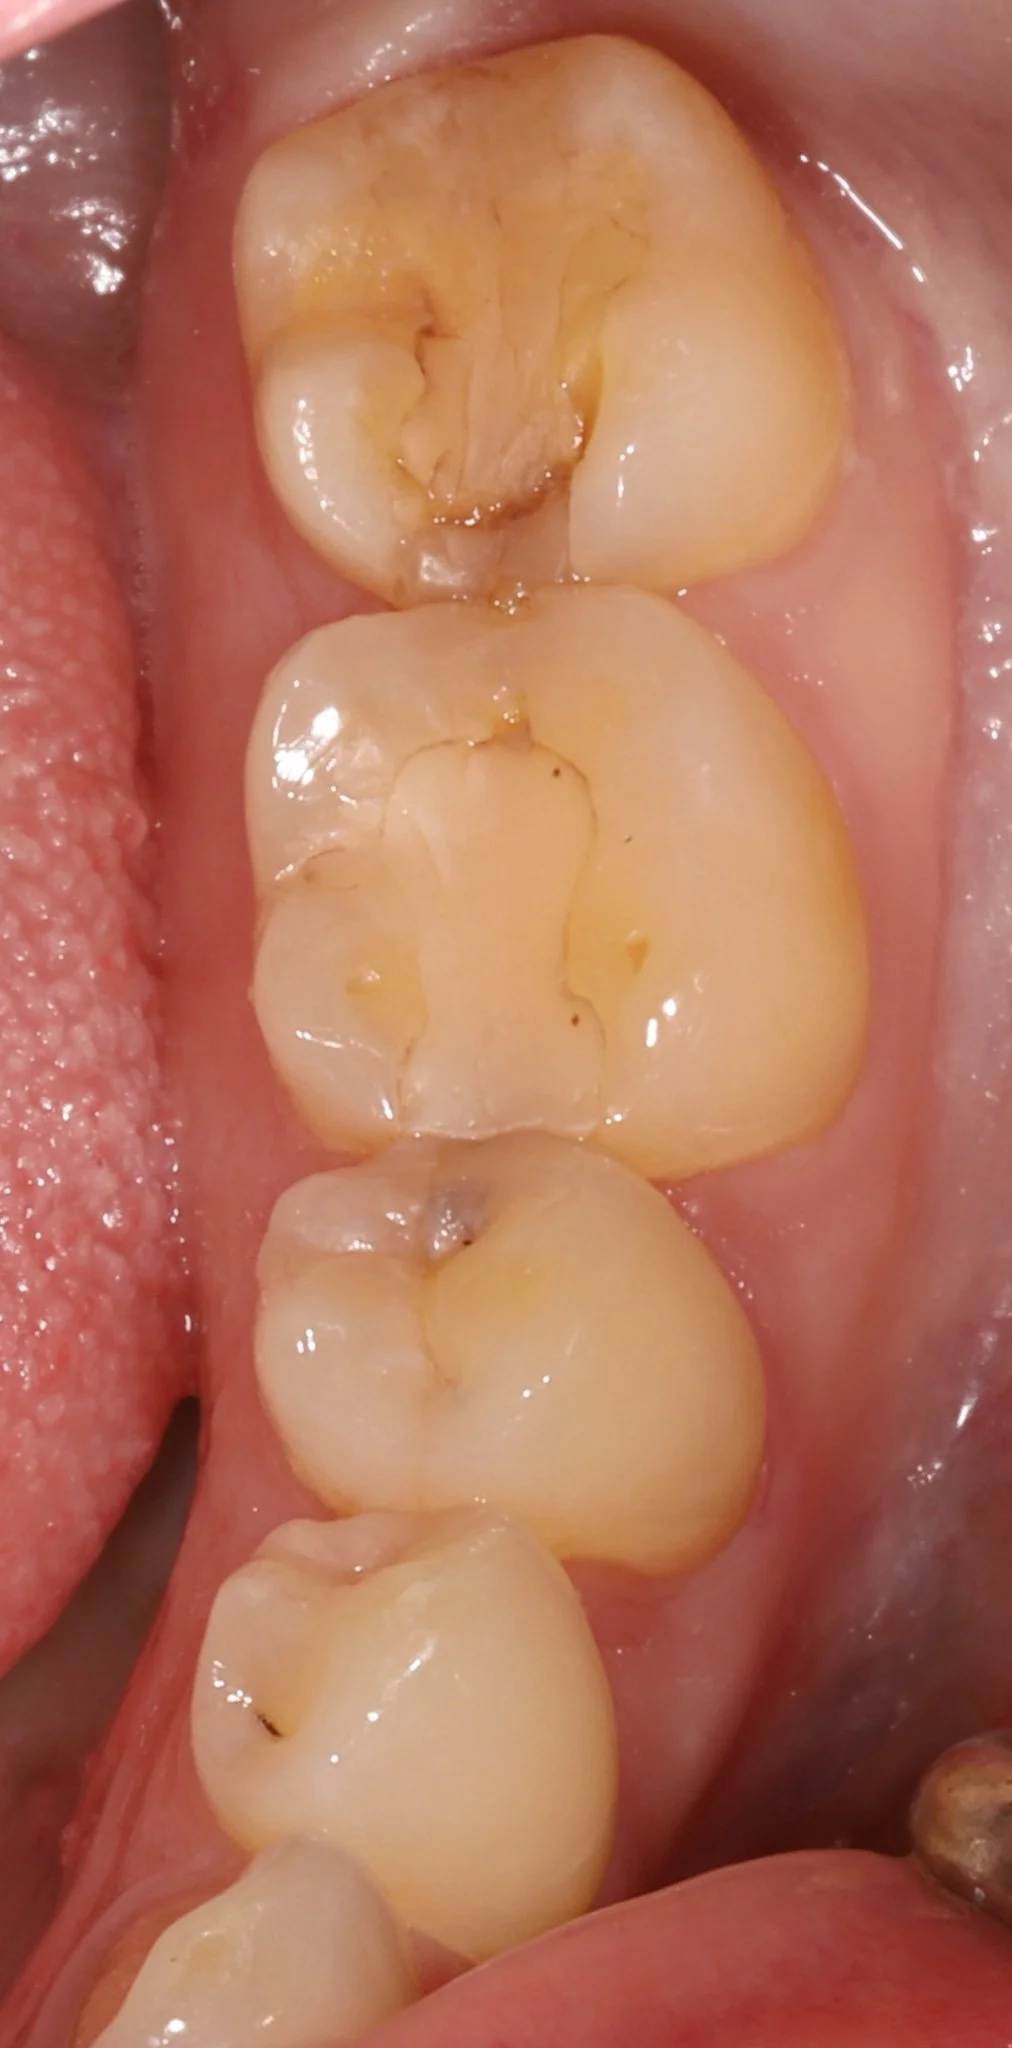

Close-up view of upper molars in a person's mouth showing dental fillings, decay and broken crowns.

Before: Decay, cracked teeth, worn teeth, poor fit

Close-up of molar teeth with signs of decay, leakage and cracks. Prior to restorative treatment.

Before: Leaking fillings, decay, cracked teeth